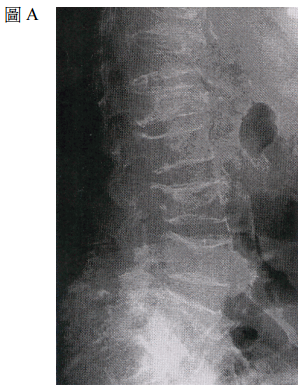

28 47 歲婦女,子宮不正常出血,使用荷爾蒙治療 3 個月無法獲得改善,子宮鏡檢查結果如下圖。最可 能的診斷是:

(A)子宮黏膜下肌瘤(submucosal myoma) (B)子宮漿膜下肌瘤(subserosal myoma) (C)子宮內膜息肉(endometrial polyp) (D) Asherman’s syndrome